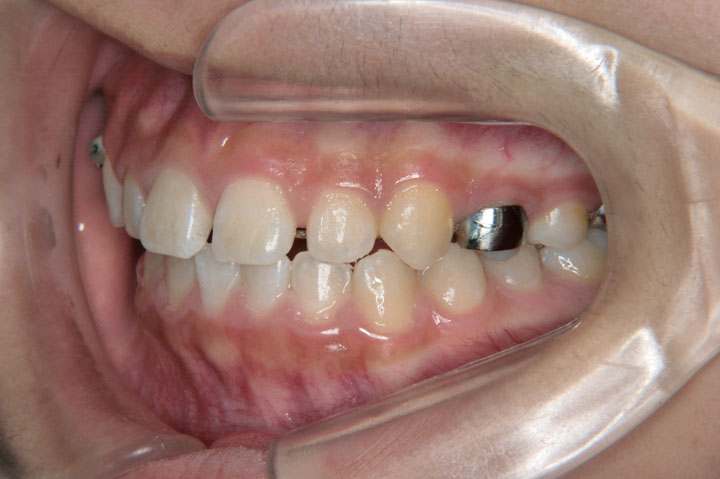

下顎の偏位と上顎右側小臼歯の萌出空隙が無いことを主訴に来院された小学校5年生の患者さんです。上顎第二大臼歯萌出前でしたので、リンガルアーチとセクショナルアーチを用いて第一大臼歯の遠心移動から開始しました。その後、非抜歯でデーモンブラケットを用いたエッジワイズ装置に移行しております。ほぼ一歯分の空隙不足でしたが、第二大臼歯萌出前に治療を開始できたことが非抜歯での矯正治療を行う上で、良かったと考えております。